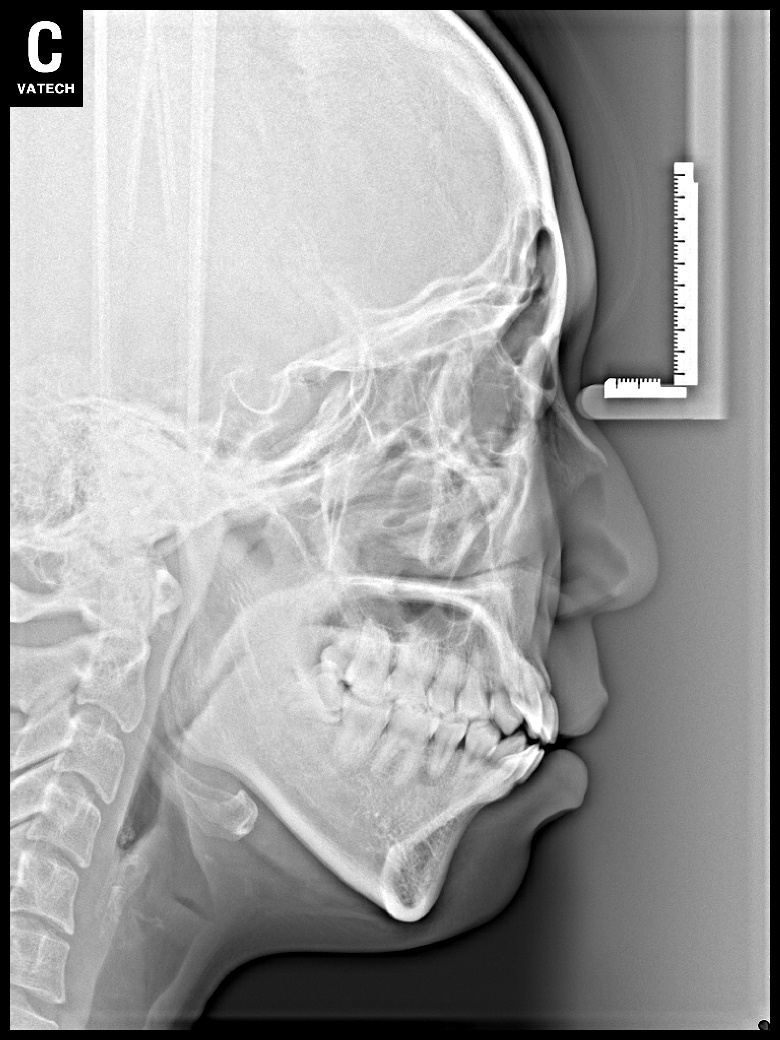

치료 전 사진입니다.